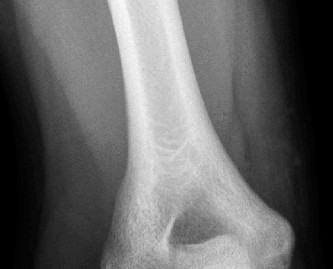

A 9-year-old, baseball pitcher presents to the office with 4 weeks of elbow pain of his throwing arm. He deni…

A 55-year-old, right-hand-dominant male presents to the office complaining of medial-sided, right elbow pain …

A 54-year-old male presented to the ED with left elbow pain after sustaining an injury in a low speed motor v…

A 16-year-old male baseball player presents to your office for evaluation of his worsening right elbow pain. …

A 14-year-old baseball pitcher presents to the office with left throwing elbow pain for the past two months w…